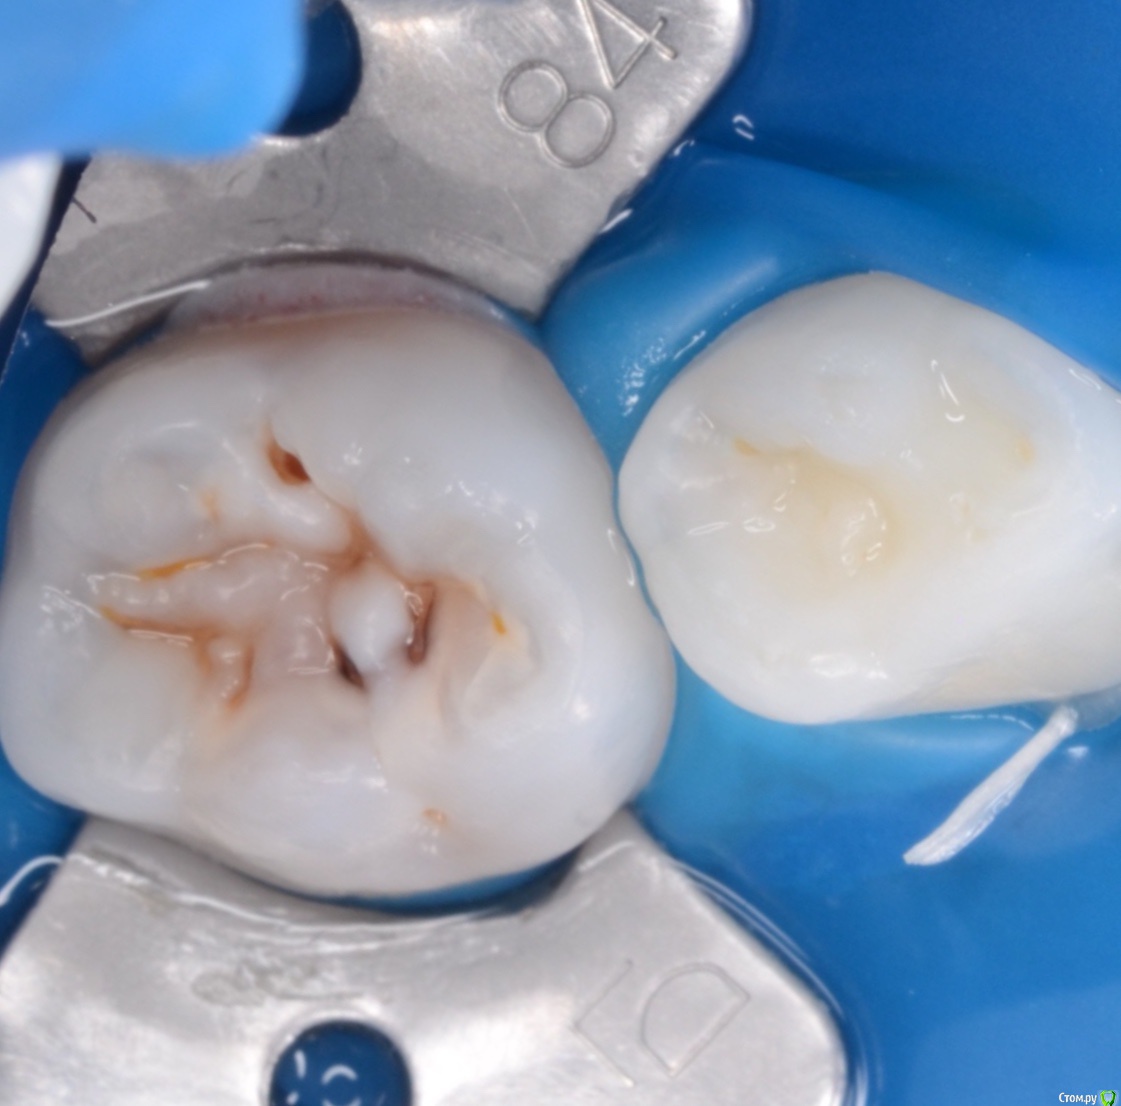

CRAZYDUCK Опубликовано 3 мая, 2018 Автор Поделиться Опубликовано 3 мая, 2018 Просто кариесули 7.4 и 7.5Обязательно убираем миловидную эмаль по контактам ( красной стрелкой на 7.5 указала )Обратите внимание , что rvg практически не визуализирует кариес медиально на 7.5 6 Ссылка на комментарий